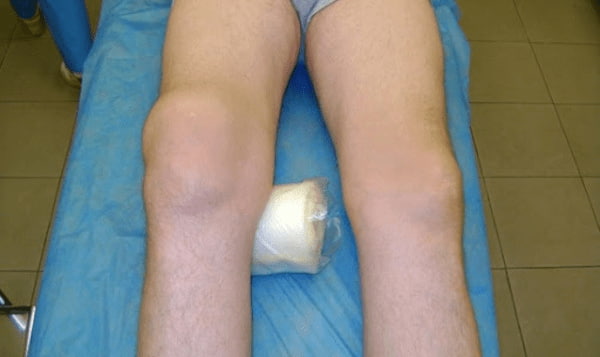

Візьміть до уваги знімок колінного суглоба 63-річного пацієнта за 1 місяць користування Artrolife - суглоб повністю регенерувався.